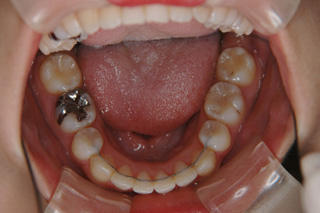

(上下顎前突/上下顎小臼歯抜歯)

装置撤去です。動的処置は2年弱でしたので、歯の移動させた距離で考慮すると、比較的短い治療期間でした。極めてよい咬合状態が得られたと思います。いずれも強い固定源を利用した結果の成果と考えられます。まだ、オーソアンカー SMAPシステム がそのまま残っているのが見えますが、もう必要ないので撤去して貰う予定です。今後は保定治療に移行し、数年にわたって咬合の安定状態を管理していきます。